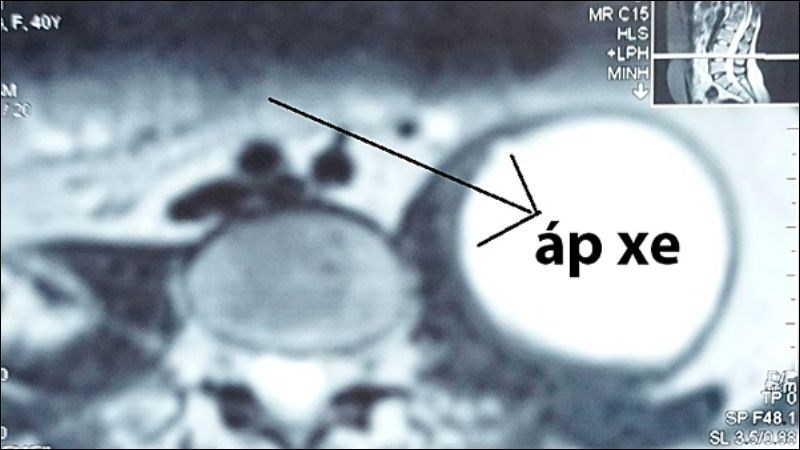

- Khi vi khuẩn phát triển, chui qua dây chằng bẹn, xuống đùi hình thành áp xe. Khi áp xe dưới da quá lớn sẽ vỡ dẫn đến hiện tượng rò mủ dưới da gây đau nhức.

- Tình trạng viêm, áp xe,... trở nặng và gây chèn ép thần kinh xung quanh đốt sống dẫn đến yếu, thậm chí liệt hai chân hoặc tứ chi, rối loạn cảm giác vùng chậu khiến đại tiểu tiện không tự chủ,...

Tình trạng viêm, áp xe trở nặng và gây chèn ép thần kinh xung quanh đốt sống

Bác sĩ có thể phát hiện tình trạng viêm đĩa đệm đốt sống do lao, hẹp khe liên đốt, phá hủy thân đốt sống, mức độ áp xe hoặc những tổn thương khối cơ do áp xe thông qua những xét nghiệm hình ảnh:

- Áp xe cạnh sống lớn chèn ép các bộ phận.